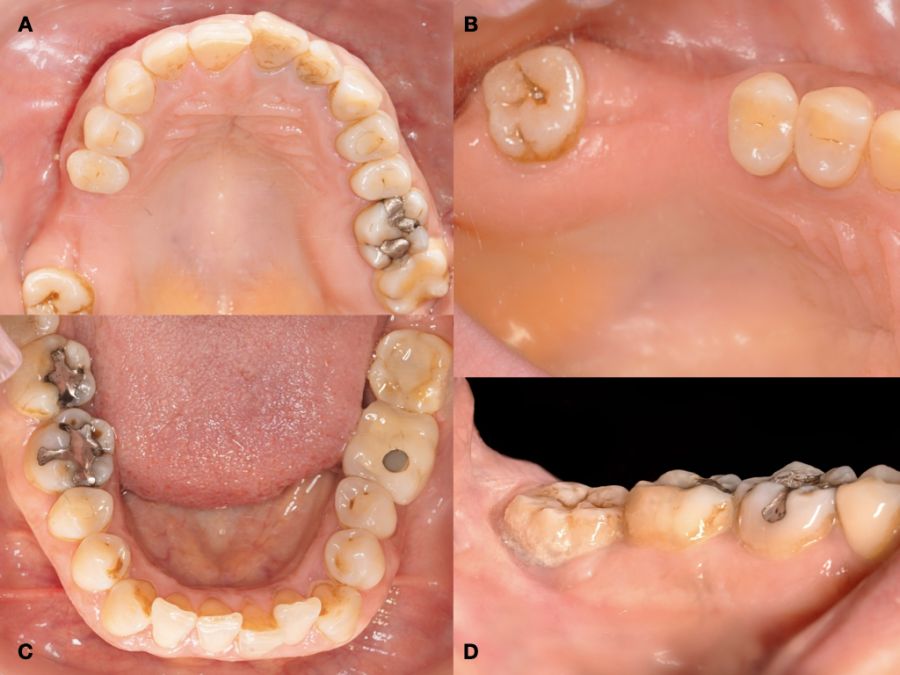

Se presenta un caso clínico de una mujer de 48 años, que acudió a consulta para reponer el sector posterior del primer cuadrante.

En la historia clínica, no se evidenciaron antecedentes médico-quirúrgicos de interés, alergias medicamentosas conocidas ni hábitos nocivos. A la exploración intraoral, se apreciaron las ausencias de 1.6 y 1.7 y la presencia del 1.8 y 4.8 (Figura 1). En la exploración radiográfica mediante escáner de haz cónico (CBCT) se apreció una altura residual de 5,0 mm en 1.6, donde se podría colocar un implante simultáneo, y de 2,6 mm en la zona del 1.7, dificultando la colocación de un implante de manera simultánea a la elevación de seno de acceso lateral (Figura 2).

Se planificó la exodoncia del 4.8 para utilizarlo como diente donante, para lo que se firmó previamente el consentimiento informado. Se realizó un bloqueo anestésico mediante articaína (Inibsa®, Barcelona, España) al 4% con adrenalina 1:100.000 del nervio dentario inferior, del nervio lingual y, por último, del nervio bucal. Al ser un diente sin procesos infecciosos asociados, únicamente se eliminó del diente el cálculo mediante instrumental ultrasónico y se realizó la extracción de la forma más atraumática posible. Se pulió la superficie radicular con fresas de diamante de turbina con abundante irrigación, eliminando de esta forma el ligamento periodontal (Figura 3).